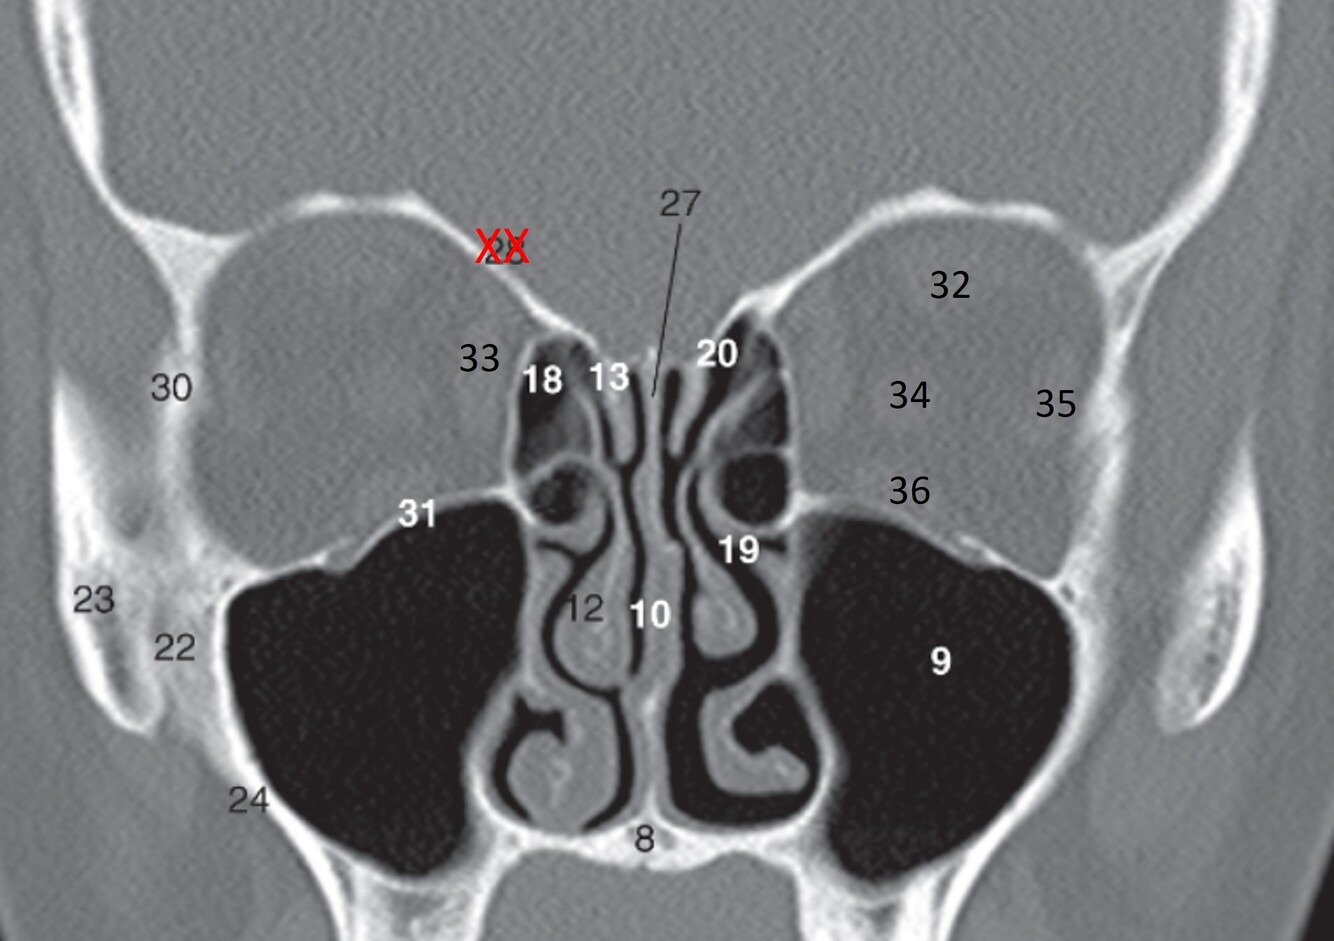

6

Label 7-12

7=Crista Galli (Ethmoid)

8.=Hard palate (Maxilla)

9=Rt. Maxillary sinus

10=Nasal septum

11=Rt. Inferior nasal concha

12=Rt. Middle nasal concha

7

Label 14,15,17,25,26

14=Rt. Inferior nasal meatus

15=Rt. Lamina papyracea (Ethmoid)

17=Rt infraorbital foramen (Maxilla)

25=Rt Orbital roof (frontal bone)

26=Rt Cribriform plate (Ethmoid)

8

Label 27-29

27=Lt Zygoma

28=Zygomatic process (Lt Maxilla)

29=Alveolar process (Rt Maxilla)

9

Label 8,9,10,12,13,18

8=Hard palate (Maxilla)

9=Lt maxillary sinus

12= Rt. Middle nasal concha

13=Rt. Superior nasal concha

18=Rt. Ethmoid air cells

10

Label 20,22,23,24,27,30,31

20-Lt. Superior nasal meatus

22=Rt maxilla (zygomatic process)

23=Rt zygoma

24=Lateral wall of Rt maxillary sinus

27=Perpendicular plate (ethmoid)

30=Rt. Lateral orbital wall (zygoma)

31=Rt. Orbital floor (maxilla)